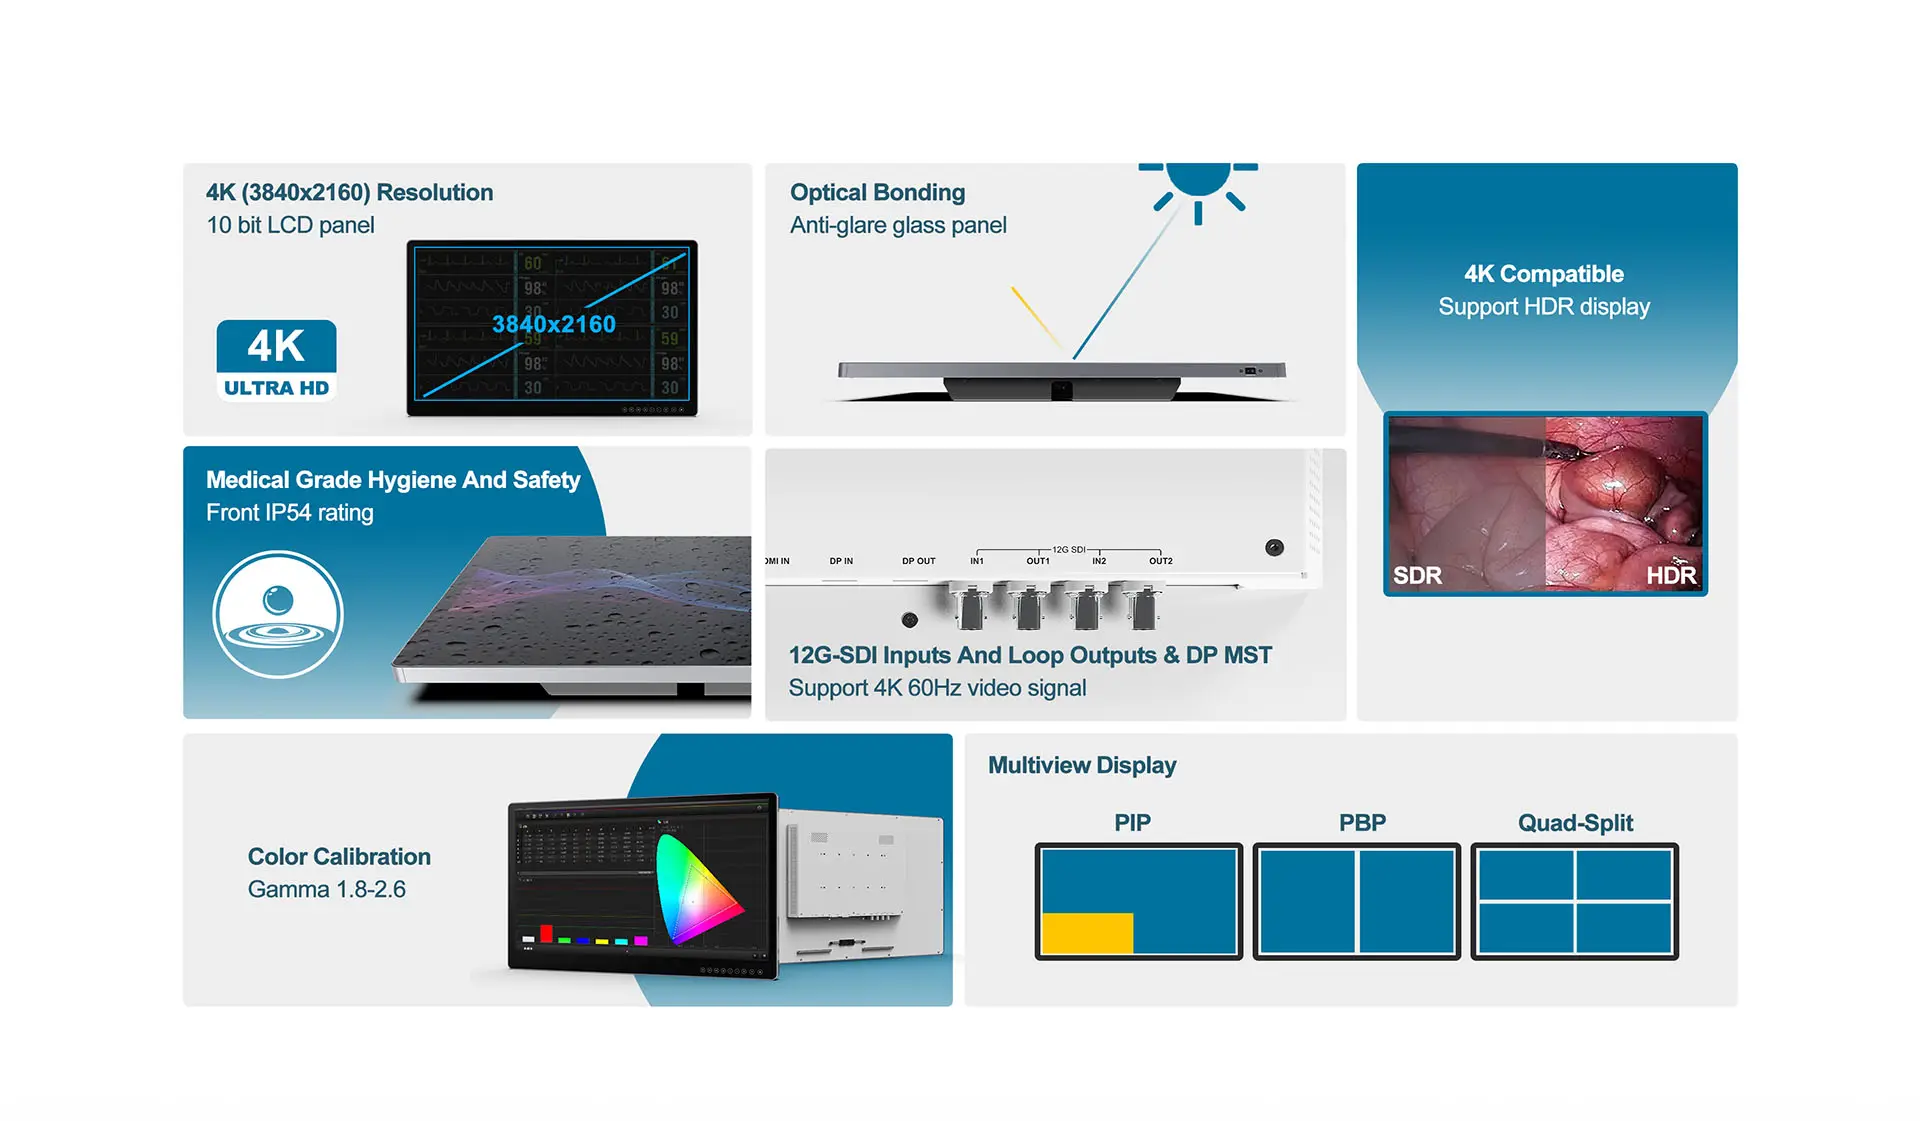

- Optical bonding process, anti-glare glass panel

- Anti-reflective, anti-fingerprint coating

- 4K (3840x2160) resolution, 10 bit LCD panel

- REC709 & BT.2020 4K compatible, support HDR display

- Color calibration gamma 1.8 - 2.6, compliant with DlCOM Part 14

- Multiview display (Dual screen / PlP / PBP / Quad-Split)

- IP54 rating for front panel

- 12G-SDl video signal input and loop-through